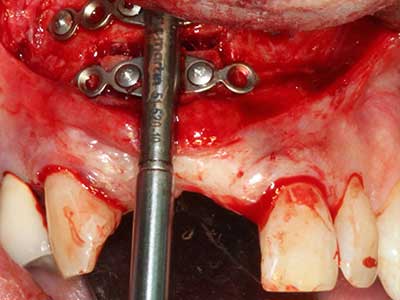

When surgical procedures are performed on bone in the immediate vicinity of sensitive structures such as blood vessels or nerves, rotary instruments pose a significant risk of iatrogenic injury. Piezoelectric devices can be helpful for preparation of bone covers and removal of hard tissue close to nerves, particularly for exposure of nerves after iatrogenic injury but also during nerve lateralization for resective and reconstructive procedures or implant placement (Fig. 17-20). Light contact between the piezotip and the nerve does not generally result in damage but proceeding incautiously with saw-like motions or attachments where a residual bone substrate remains may cause temporary or even permanent nerve damage. However, the risk of damage is considered to be substantially lower than when using saws or milling instruments (Pereira, Gealh et al. 2014).

As shown in the past, basically any bone surgery procedure represents a possible indication for piezo surgery. Thus preparation of the mobile segment in distraction osteogenesis (Fig. 23-25) and sandwich osteotomy uses special attachments without endangering the blood supply to the crestal section, which is essential for the success of both techniques (Gonzalez-Garcia, Diniz-Freitas et al. 2008).

Purely orthodontic indications include orthognathic surgery, genioplasty (Fig. 27-30) and orbital decompression in patients with advanced endocrine orbitopathy as a result of Basedow’s disease (Ponto, Zwiener et al. 2014). Piezo devices are also used in maxillofacial surgery and to remove tumours at the base of the skull in various hospitals.